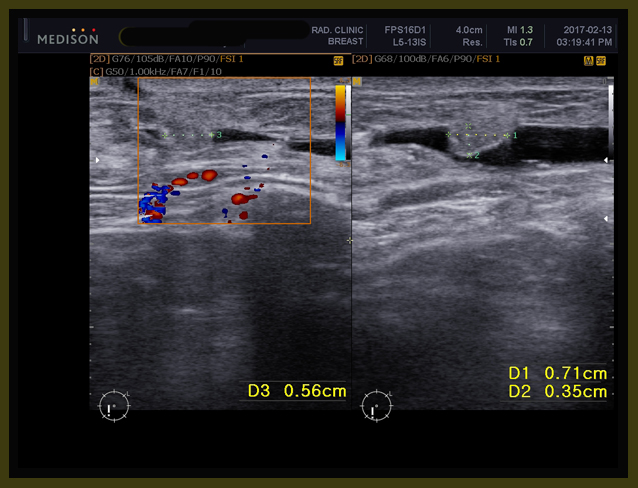

이 환자는 프로게스테론이 tamoxifen을 사용하는 중에 본원에 오게 되었고 나는 이 환자의 초음파를 의뢰하였다. 여기서 덧붙이면 소양인에게는 엽산이 적합하지 않다. 엽산의 결핍으로 임신에 문제를 일으키는 체질은 소음인이다. 최근에도 내게 온 소음인이 인공수정을 계속 실패하여서 임신이 되었다가 7주부터 12주 사이에 3회나 유산이 되었다고 하였다. 그리하여 엽산에 관한 유전자 검사를 하였더니 전혀 엽산흡수가 안되는 체질이라고 하여서 엽산을 보통 농도의 10배 정도를 섭취하고 나서야 임신유지가 되어서 넷째 때는 성공을 하였다고 하였다. 나의 생각으로는 엽산은 estrogenic한 작용이 있다고 본다. 에스트로겐을 높이는 역할을 한다고 추론된다. 그래서 에스트로겐이 부족한 소음인들은 사용하면 좋은 결과가 오지만 기타 체질은 엽산의 사용이 오히려 문제가 될 수가 있다. 이 환자도 이전에 임신시에 엽산을 복용하자 너무 구토가 심하게 올라와서 할 수 없이 엽산을 중지한 경험이 있다. 이는 엽산이 도와주는 에스트로겐의 역할이 소양인은 항진 되어 있어서 더 보태면 이 같은 부작용이 나타날 수가 있다.

환자는 1년 전에 난소의 양성종양으로 수술을 받았던 경험이 있고, 이번에도 유방수술 이후에 초음파를 보니 83mm x 61 mm x 58 mm의 약 8cm x6cm 정도의 격벽으로 분리된 cystic mass 즉 액상의 종양이 보였고, 또한 13mm, 15 mm의  mass도 발견되었다(2017년 1월 26일 검사).

내원 후에 본원 의뢰하여서 초음파 검사를 하였는데 초음파상의 결과는 이전 병원과 약간의 차이가 있지만 역시 8cm가 넘는 종양이 발견되었다.

나는 요꼬 선생님께 이 환자를 의뢰하여서 그간 사용하던 tamoxifen을  aromatase inhibitor 의 한 종류인 arimidex와 metformin 합성요법을 2월 16일부터 시작하였다. 그리고 치료시작과 더불어서 이 환자의 에스트로겐 수치를 점검하였는데 에스트로겐수치가 무려 1000 이상으로 높이 나왔다.

1-4

유방암 환자에게 유방암에 특별지표인 CA -15-3을 체크를 하는데 이의 증가는 유방암의 악화나 발병을 의미한다. 하지만 모든 유방암 환자에게서 지표가 되지는 않는다. 특히 소음인 환자들은 종양의 진전과 상관없이 CA 15-3이 낮게 나타나는 경우가 많이 발견된다. 나는 소양인이 일반적인 에스트로겐 수치만 체크하여도 분명 병의 진행과 에스트로겐의 상관관계가 있으리라는 생각으로 체크를 시켰는데 역시 결과는 위에 보듯이 기준치가 평소에 배란기인 11-20일 사이가  437 로 가장 높은데 이의 두배가 넘는 1000 이상의 수치가 나왔다.